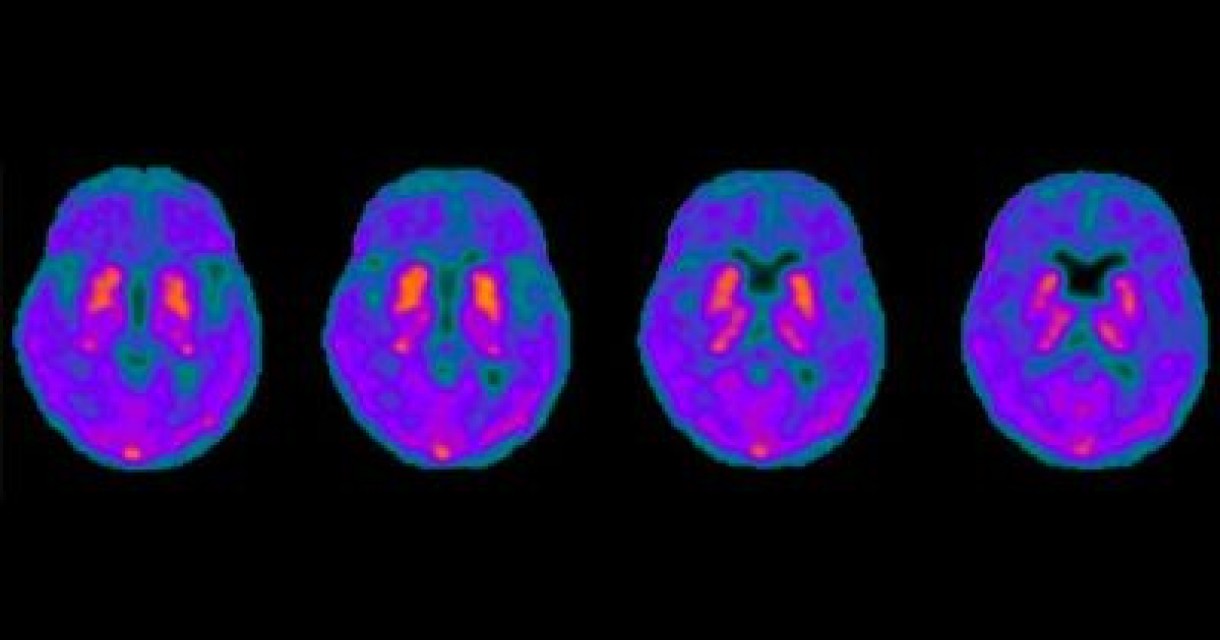

Brain Tau PET

A unique research study is underway through the New Zealand Brain Research Institute (NZBRI) with New Zealand’s first brain tau PET scan in Christchurch. The focus is on Parkinson’s disease dementia.

The study involves the use of the protein tau, a key protein involved in many neurodegenerative diseases – and the use of Positron Emission Tomography (PET) imaging techniques.

The study aims to put 50-60 people with Parkinson’s through the tau PET imaging. At NZBRI they have been undertaking a large longitudinal study for some 15 years of over 320 people with Parkinson’s. It is this group as well as some new participants, with varying degrees of Parkinson’s disease dementia, who will be invited to take part in the study. The tau radiotracer is injected into a patient’s arm. It takes some 40-45 minutes to travel to the brain. It then binds to whatever tau is deposited in the brain emitting a glow which is visible through the PET scanner.

Image courtesy of Dr Lucy Vivash, Department of Neurology, Alfred Health and Department of Neuroscience, Monash University. Brain Axial Tau Pet-CT colour-fused image.